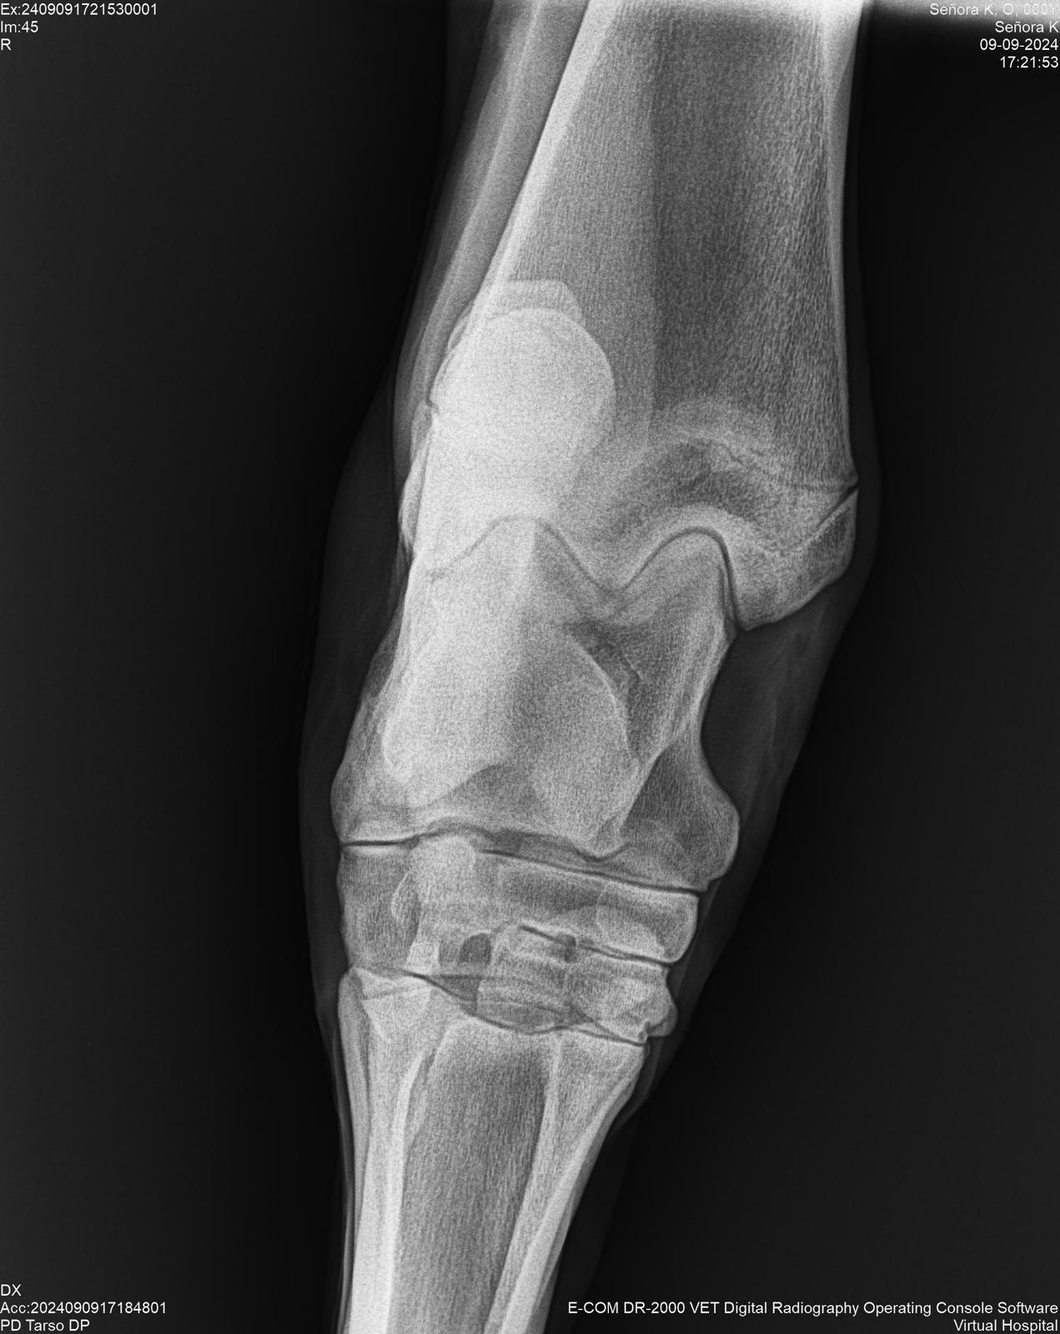

LOTE 44, SEÑORA K

Identificador: #291147-

Generacion 2022